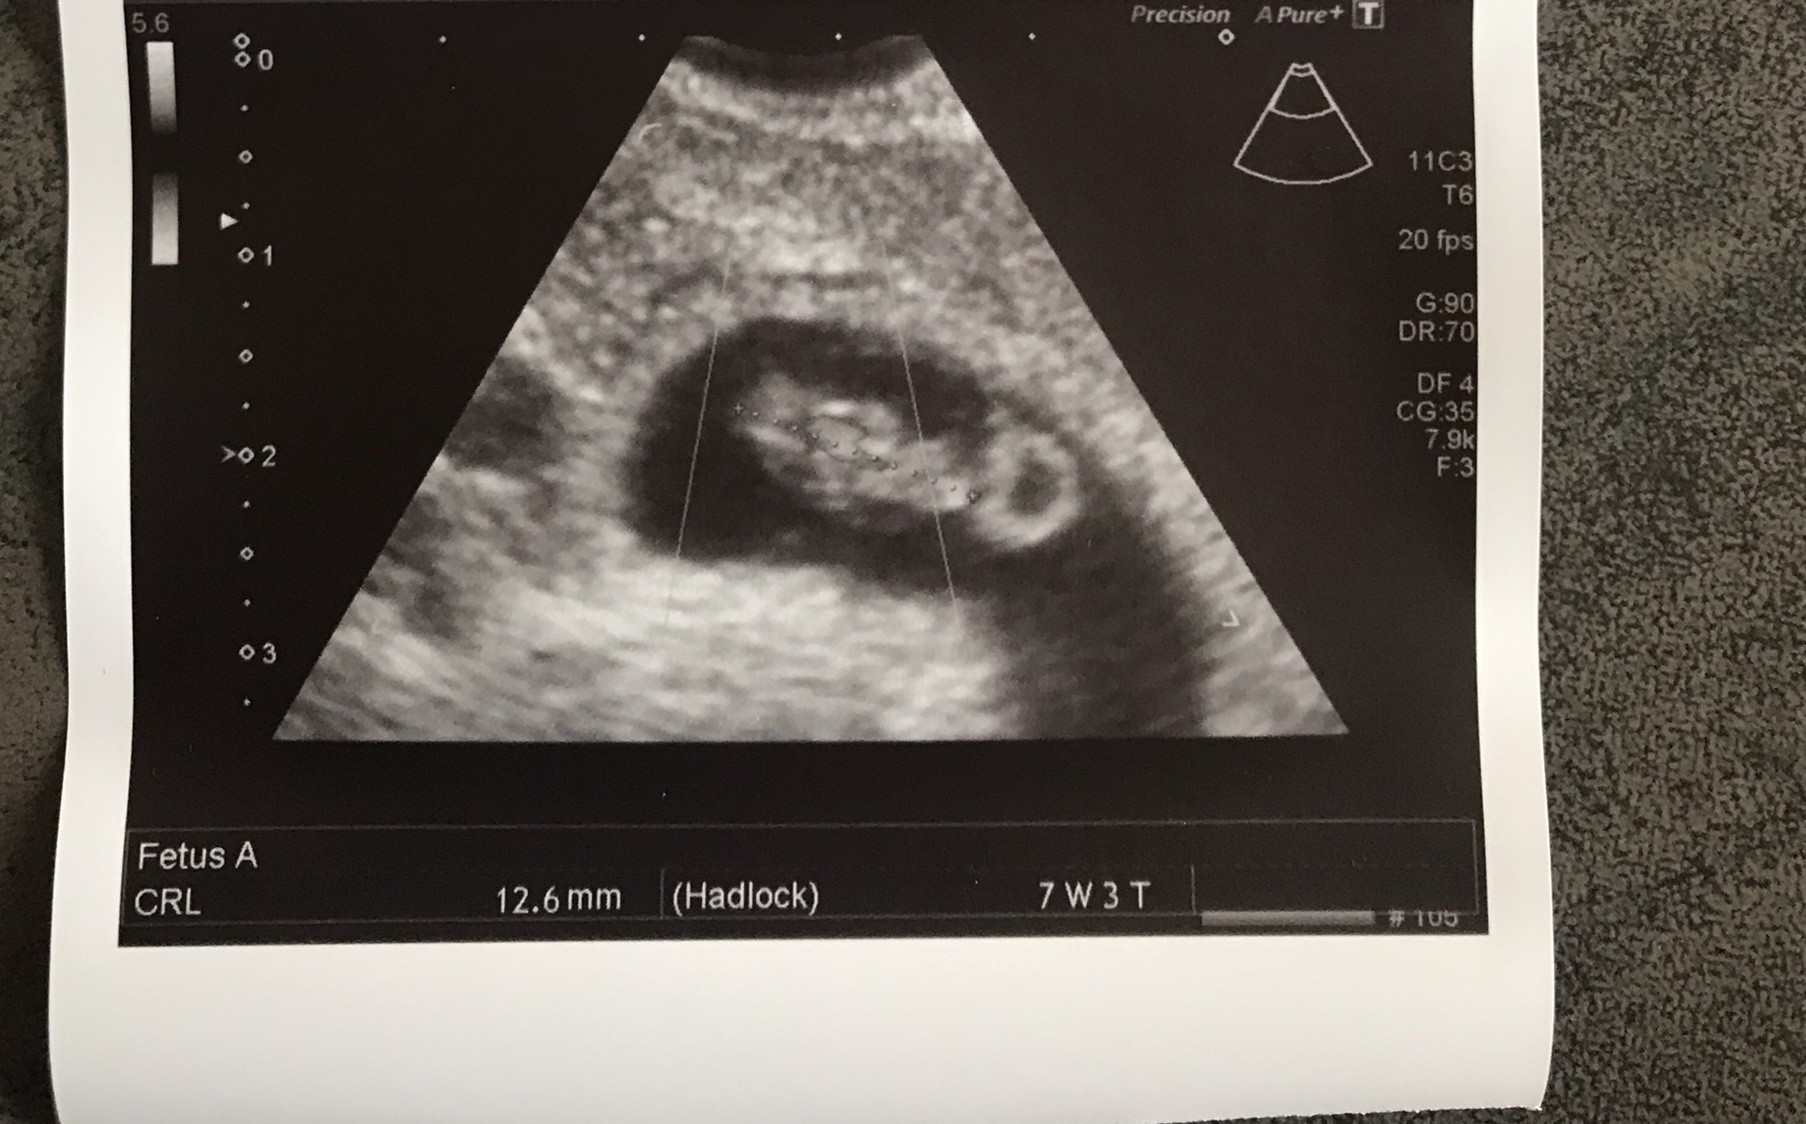

No jest mały rozrabiaka, serduszko bije, ale ciąża jest zagrożona. Mam leżeć, dostałam skierowania na badania krwi i moczu i czwartek za tydzień znowu wizyta. Mam nadzieje, ze wszystko będzie dobrze [emoji120][emoji120][emoji120][emoji120][emoji120][emoji120][emoji120]

Gratulacje kochana [emoji7] przypomnij który to tydzień u Ciebie?